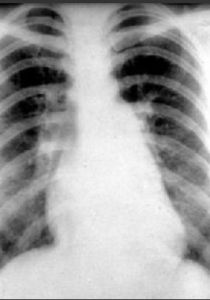

根據水腫發展的過程分為肺間質水腫期和肺泡水腫期 肺間質水腫期 症狀:病人常感到胸悶、恐懼、咳嗽、有呼吸困難。 體徵:面色蒼白、呼吸急速、心動過速、血壓升高,可聞及哮鳴音。 X線檢查:肺血管紋理模糊,肺門陰影不清楚。肺小葉間隔加寬,形成Kerley A線和B線。 血氣分析:PaCO2偏低,pH↑、呈 呼吸性鹼中毒。 肺泡水腫期 症狀: 病人面色更蒼白,更覺呼吸困難,出冷汗 等。 體徵: 口唇、甲床紫紺,湧出大量粉紅色泡沫痰,全麻病人可表現呼吸道阻力增加和發紺,經氣管導管噴出大量粉紅色泡沫痰;雙肺聽診: 滿肺濕羅音,血壓下降 X線檢查: 主要是肺泡狀增密陰影,相互融合呈不規則片狀模糊影,瀰漫分布或局限於一側或一葉,或見於肺門兩側,由內向外逐漸變淡,形成所謂蝴蝶狀典型 血氣分析: PaCO2偏高和/或PaO2下降,pH偏低,表現為低氧血症和呼吸性酸中毒診斷和鑑別診斷

肺水腫的診斷主要根據症狀、體徵和X線表現。 早期診斷方法:測定肺小動脈楔壓和 血漿膠體滲透壓,如壓差小於 4mmHg時不可避免出現肺水腫。 連續測定胸部基礎阻抗(胸腔液體指數,TFl),TFI下降揭示肺水增多。治療原則